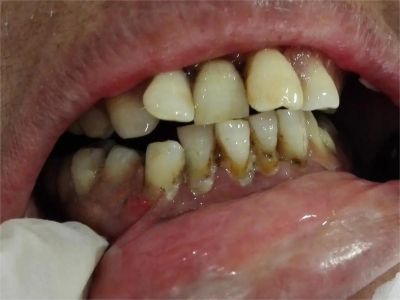

急性坏死性溃疡性龈炎起病急,病程短,常为数天至1-2周,以龈乳头和龈缘的坏死为其特征性损害,尤以下前牙多见,初起时龈乳头充血水肿,个别龈乳头顶端可发生坏死性溃疡,上覆有灰白色坏死物,中央凹下如火山口状。龈缘如虫蚀状,坏死区出现灰褐色假膜,擦去后可见出血创面。龈乳头被破坏后与龈缘成一直线,如刀切状。病损一般不波及附着龈,患处牙龈极易出血,疼痛明显并有腐败性口臭。

重症患者可有低热、疲乏等全身症状,并可伴有下颌下淋巴结肿大和压痛。有的患者可能进展为坏死性龈口炎、坏死性溃疡性牙周炎等疾病,从而导致牙周袋形成、牙槽骨吸收和牙齿松动。